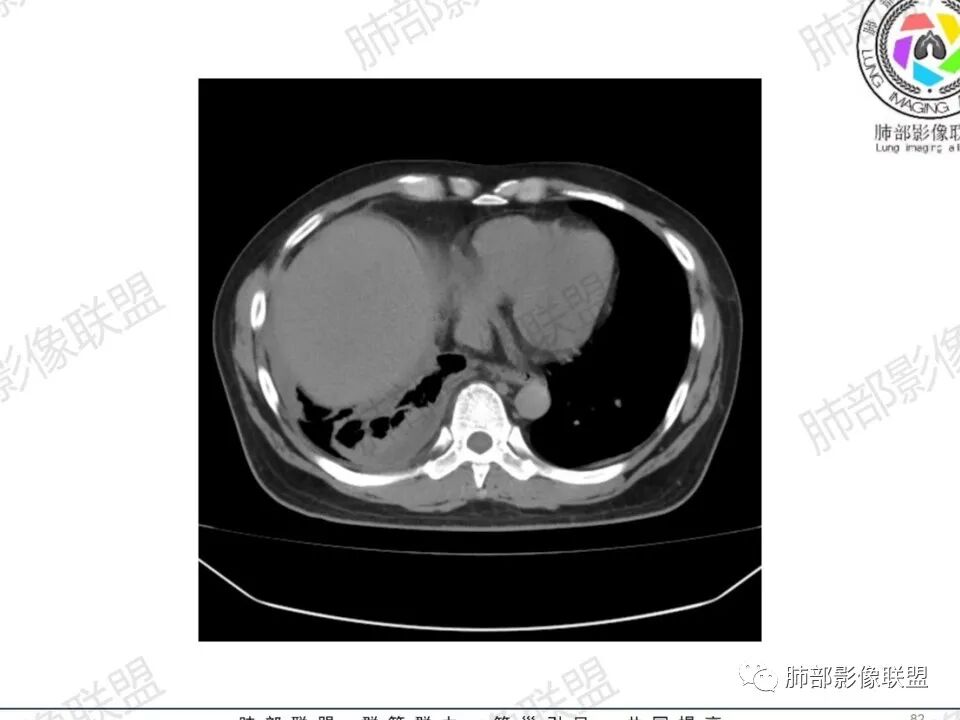

双肺多发结节,胸膜下为主,部分可见空洞。左肺上叶尖后段结节较大,分叶毛刺,周围可见长条索及小斑片影,内空洞比较光滑,内侧壁可见支气管通过。右肺下叶后基底段不张实变,后侧积液,右侧水平裂积液,右侧膈胸膜纵膈胸膜增厚积液,右侧侧胸膜肥厚,考虑1:一元金葡。2二元:金葡,左肺上叶结核。

男,45岁,左手指红肿疼痛两天,右侧胸壁疼痛伴发热12小时入院。患者急性起病,胸部CT示双肺多发结节,部分伴空洞,空洞壁较光滑,右侧胸腔积液,考虑感染性病变,金葡菌加SPE可能

中年男性,左手中指及胸壁疼痛伴发热来诊,影像见双肺多发结节,胸膜下分布为主,部分结节可见空洞,边缘模糊。左肺上叶尖后段结节较大。右肺下叶后基底段不张实变,右侧叶间裂及右侧胸腔积液,右侧侧胸膜肥厚。考虑金葡菌感染,血播SPE。

两肺多发结节空洞,随机分布,右肺下叶部分病灶实变并胸膜腔少量积液,有皮肤破溃,手指疼痛,发热,考虑感染性变,金葡可能性大。

空洞内壁光滑,偏心厚壁空洞,张力高

胸水,部分包裹